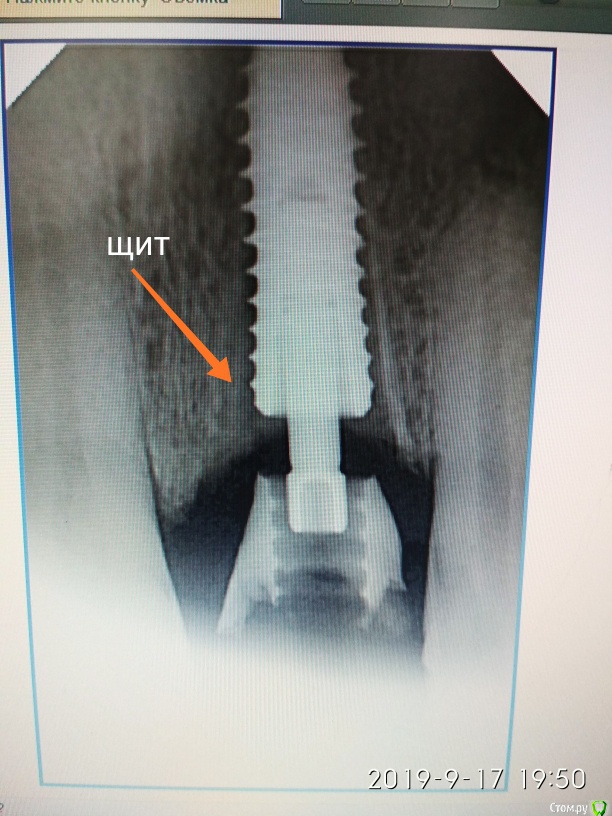

Дмитрий М Опубликовано 25 сентября, 2019 Поделиться Опубликовано 25 сентября, 2019 Пуциент 43г. перелом 21 зуба пациент без эстетических притязаний, совсем. главное, чтобы было дешево )))воксап- удаление - щит- имплантация- изготовление временной- фиксация Ссылка на комментарий

Дмитрий М Опубликовано 27 сентября, 2019 Автор Поделиться Опубликовано 27 сентября, 2019 Хорошая работа ! какой имплантант установлен?спасибо superline 4,5*12 Ссылка на комментарий